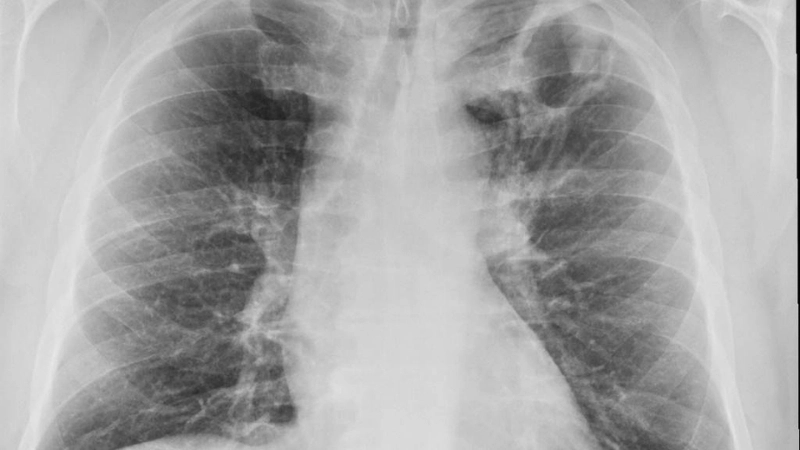

Hình ảnh x quang lao phổi điển hình